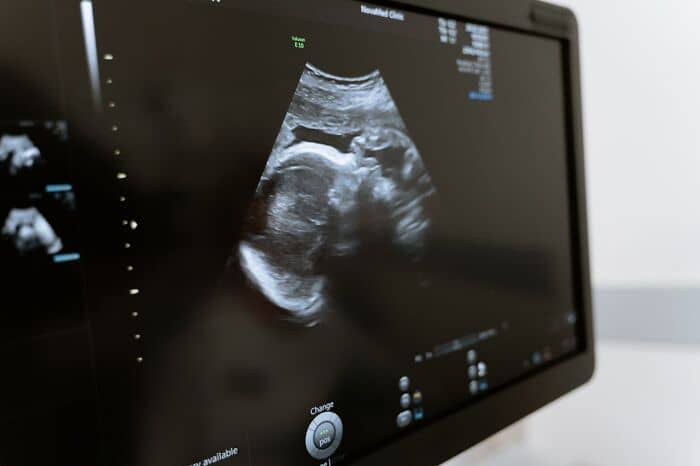

#9

When I was an ultrasound student, a woman came in for her 20wk anatomy scan. It was right before Christmas. All her family was in town, and she was going to have a gender reveal. Her baby had anencephaly (absent brain), acrania (absent skull bones), omphalocele (herniation of the intestines into the cord), and a club foot. The Ob doc asked her if she wanted to be induced right then and there or wait until after the holidays. She chose to terminate her pregnancy immediately. I can’t even imagine how she was feeling. The baby looked like an alien.